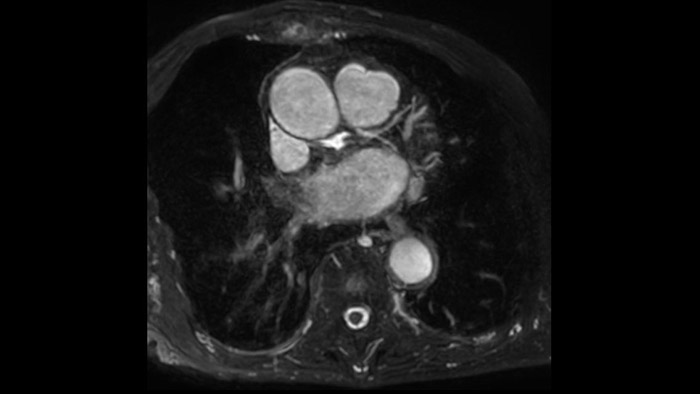

IntelliSpace Portal MR Caas7,8 A solução de pós-processamento 4D Flow permite a geração de reconstruções de volume 3D, para visualizar e avaliar o fluxo sanguíneo em estruturas cardiovasculares, incluindo válvulas cardíacas, câmaras e vasos, com base nas imagens de RM 4D Flow cardiovascular.